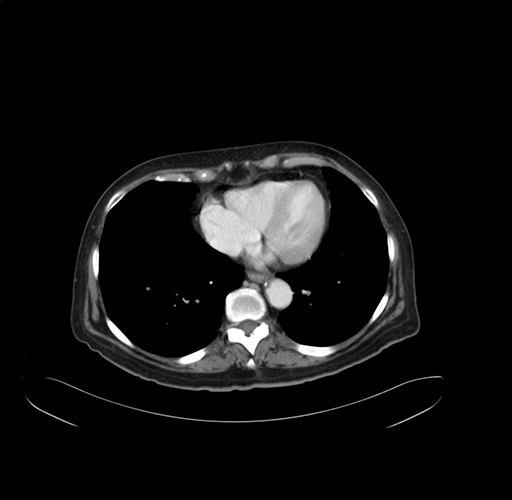

Pre-Chemo: Axial Venous

Axial Venous